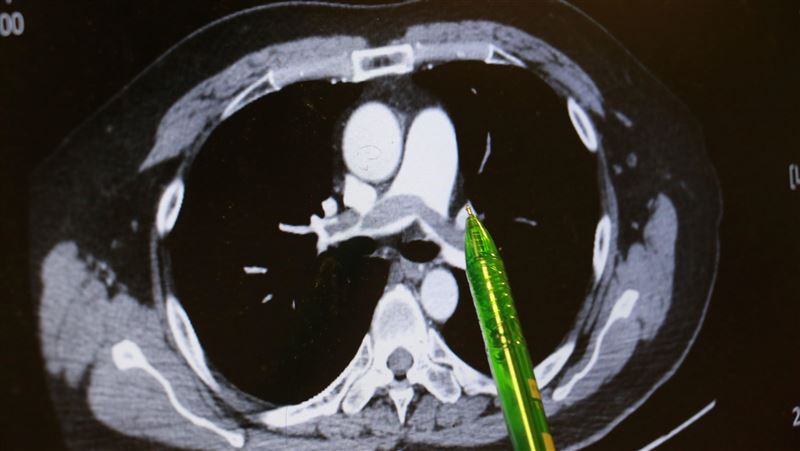

▲病人肺部兩側大片瀰漫的血栓。(圖/台中慈濟醫院)

謝姓男子不菸不酒,但他自述上班久坐、在家也習慣久躺沙發,回想發病當天走樓梯時,短短一層樓竟像是爬長陡坡,路過同事發現他喘不過氣、唇色發綠、冷汗直冒,催促緊急就醫。急診醫師檢查發現男子血氧飽和度指數極低,電腦斷層顯示雙側肺動脈都有大塊血栓,會診心臟內科主任林茂仁確認是「雙側肺栓塞」。

林茂仁說明,男子兩側肺葉瀰漫大片血栓,屬於臨床典型而嚴重的「肺栓塞」,幸好他馬上到急診就醫,還主述一周前曾出現「單側小腿腫脹」的重要訊息,再透過相關檢查,幫助醫師快速查出病因。值得注意的是,病人血液檢查發現具有家族性先天凝血因子異常,顯示體質天生比一般人有更多發生血栓的機會。病人證實,雙親都罹患心血管病史,近半年來迷上網路小說,常久躺沙發幾個小時都不起身。